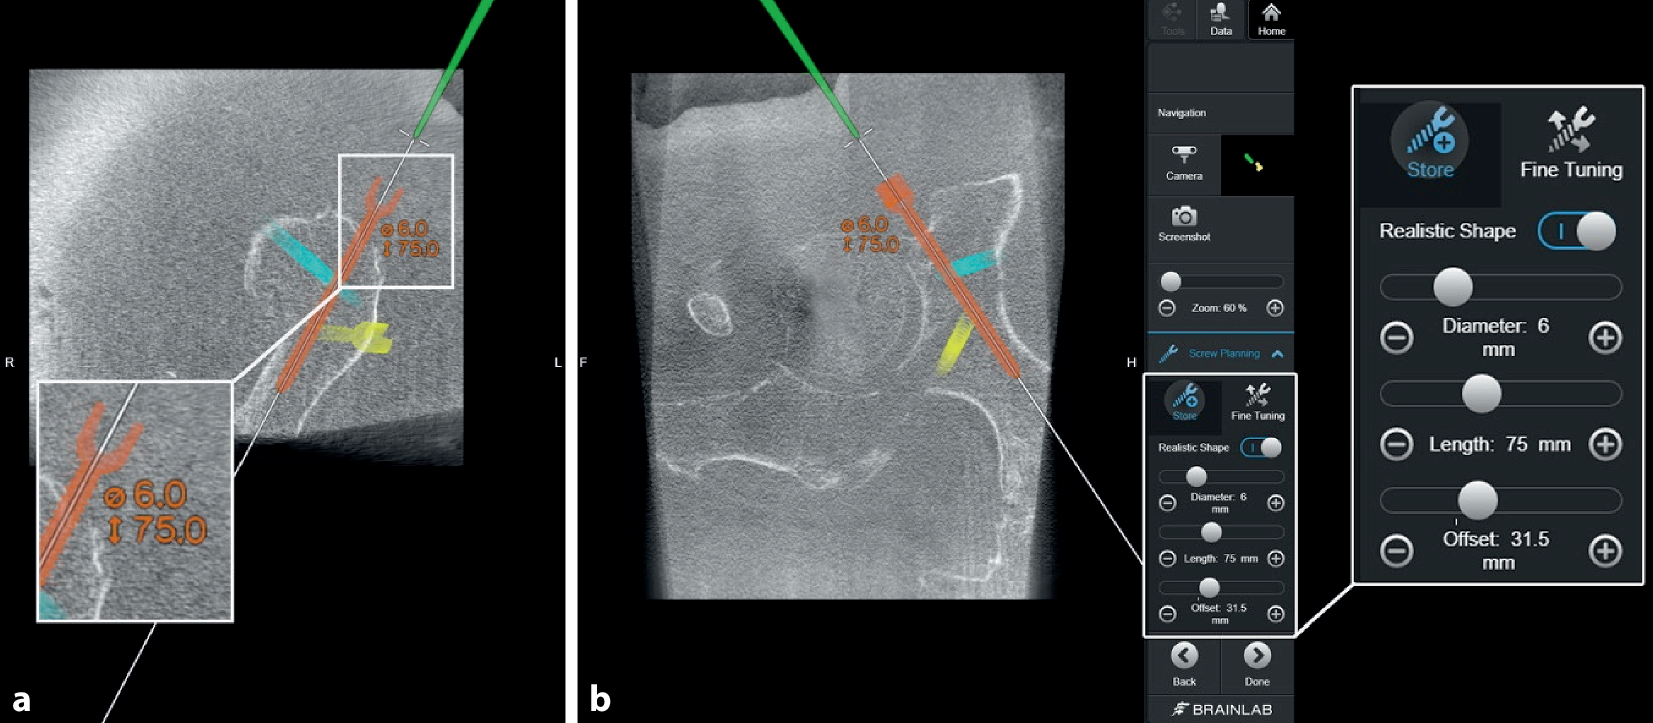

Abb. 8

Über das Interface des Navigationssystems werden mithilfe des Pointerinstrumentariums mögliche Schraubenpositionen eruiert und geplant. Hierbei können bereits die Schraubenlänge und Durchmesser kontrolliert (a) und über das Menü bei Bedarf angepasst (b) und eventuelle Schraubenkorridore so geprüft werden

Abb. 9

Die Planung der Schrauben kann dann nochmals manuell über den Touchscreen feinjustiert werden, um eventuelle intraartikuläre Fehllagen zu vermeiden